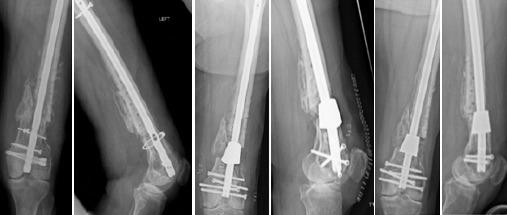

Segmental bone loss in the distal femur presents a challenge for reconstruction regardless of etiology. Use of tantalum trabecular metal cones with intramedullary fixation and autologous bone graft may be used as a salvage technique in difficult situations where other options have either been exhausted or are unavailable.

Surgical planning and technique for this approach to reconstruction are described. A retrospective review of five cases with >1 year of follow-up was performed to provide radiographic and clinical outcomes. All five patients had satisfactory outcomes with clinical union and retention of implants at final follow-up (average >4 years).

Use of tantalum metal cones for reconstruction of distal femur nonunion with segmental bone defects can be a successful technique in a complex group of patients.